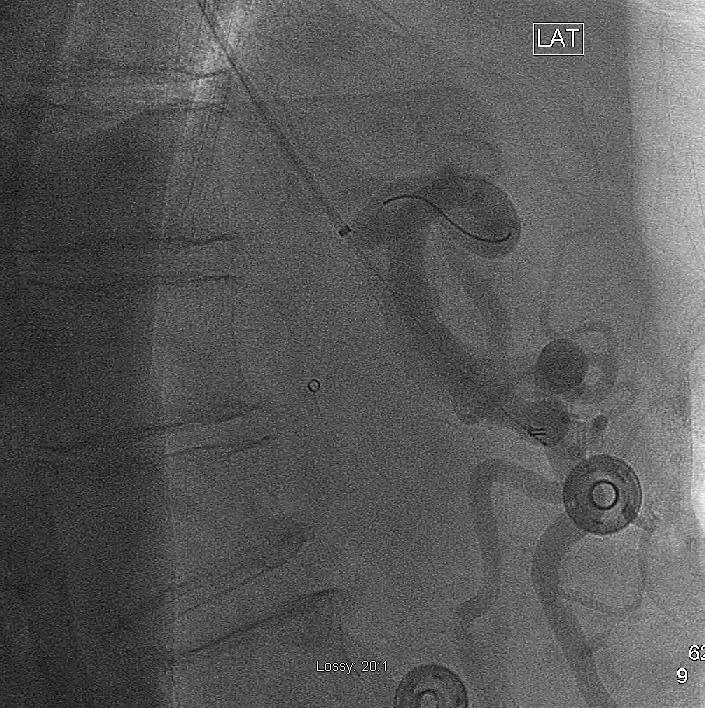

Following treatment of restenosis, there was rapid flow of contrast into the splenic and common hepatic arteries (Fig 3).

Mesenteric artery intervention

Selective injection of the celiac artery showing a patent proximal stent post-angioplasty. The wire tip is visible in the splenic artery in this lateral projection.

At subsequent annual follow-up visits, the patient has not complained of symptoms, though surveillance ultrasound has demonstrated increased celiac artery velocities with a patent stent.